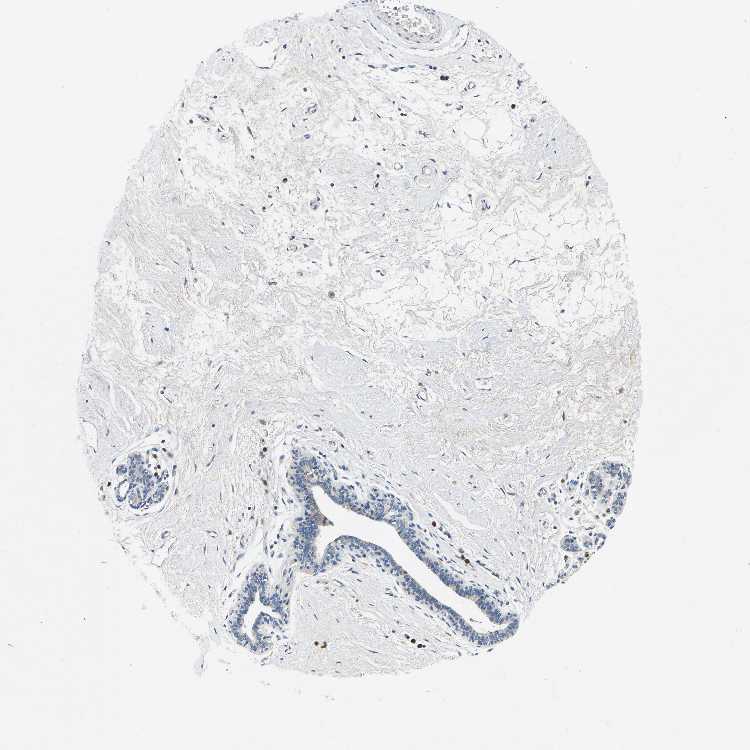

BREAST - Antibody stainingi

Antibody staining in the annotated cell types in the current human tissue is reported as not detected, low, medium, or high, based on conventional immunohistochemistry profiling in selected tissues. This score is based on the combination of the staining intensity and fraction of stained cells.

Each image is clickable and will lead to virtual microscopy that enables deeper exploration of all samples and also displays staining intensity scores, fraction scores and subcellular localization as well as patient and tissue information for each sample.

Antibody HPA015242Antibody HPA015968

Adipocytes Not detectedNot detected

Glandular cells MediumNot detected

Myoepithelial cells Not detectedNot detected